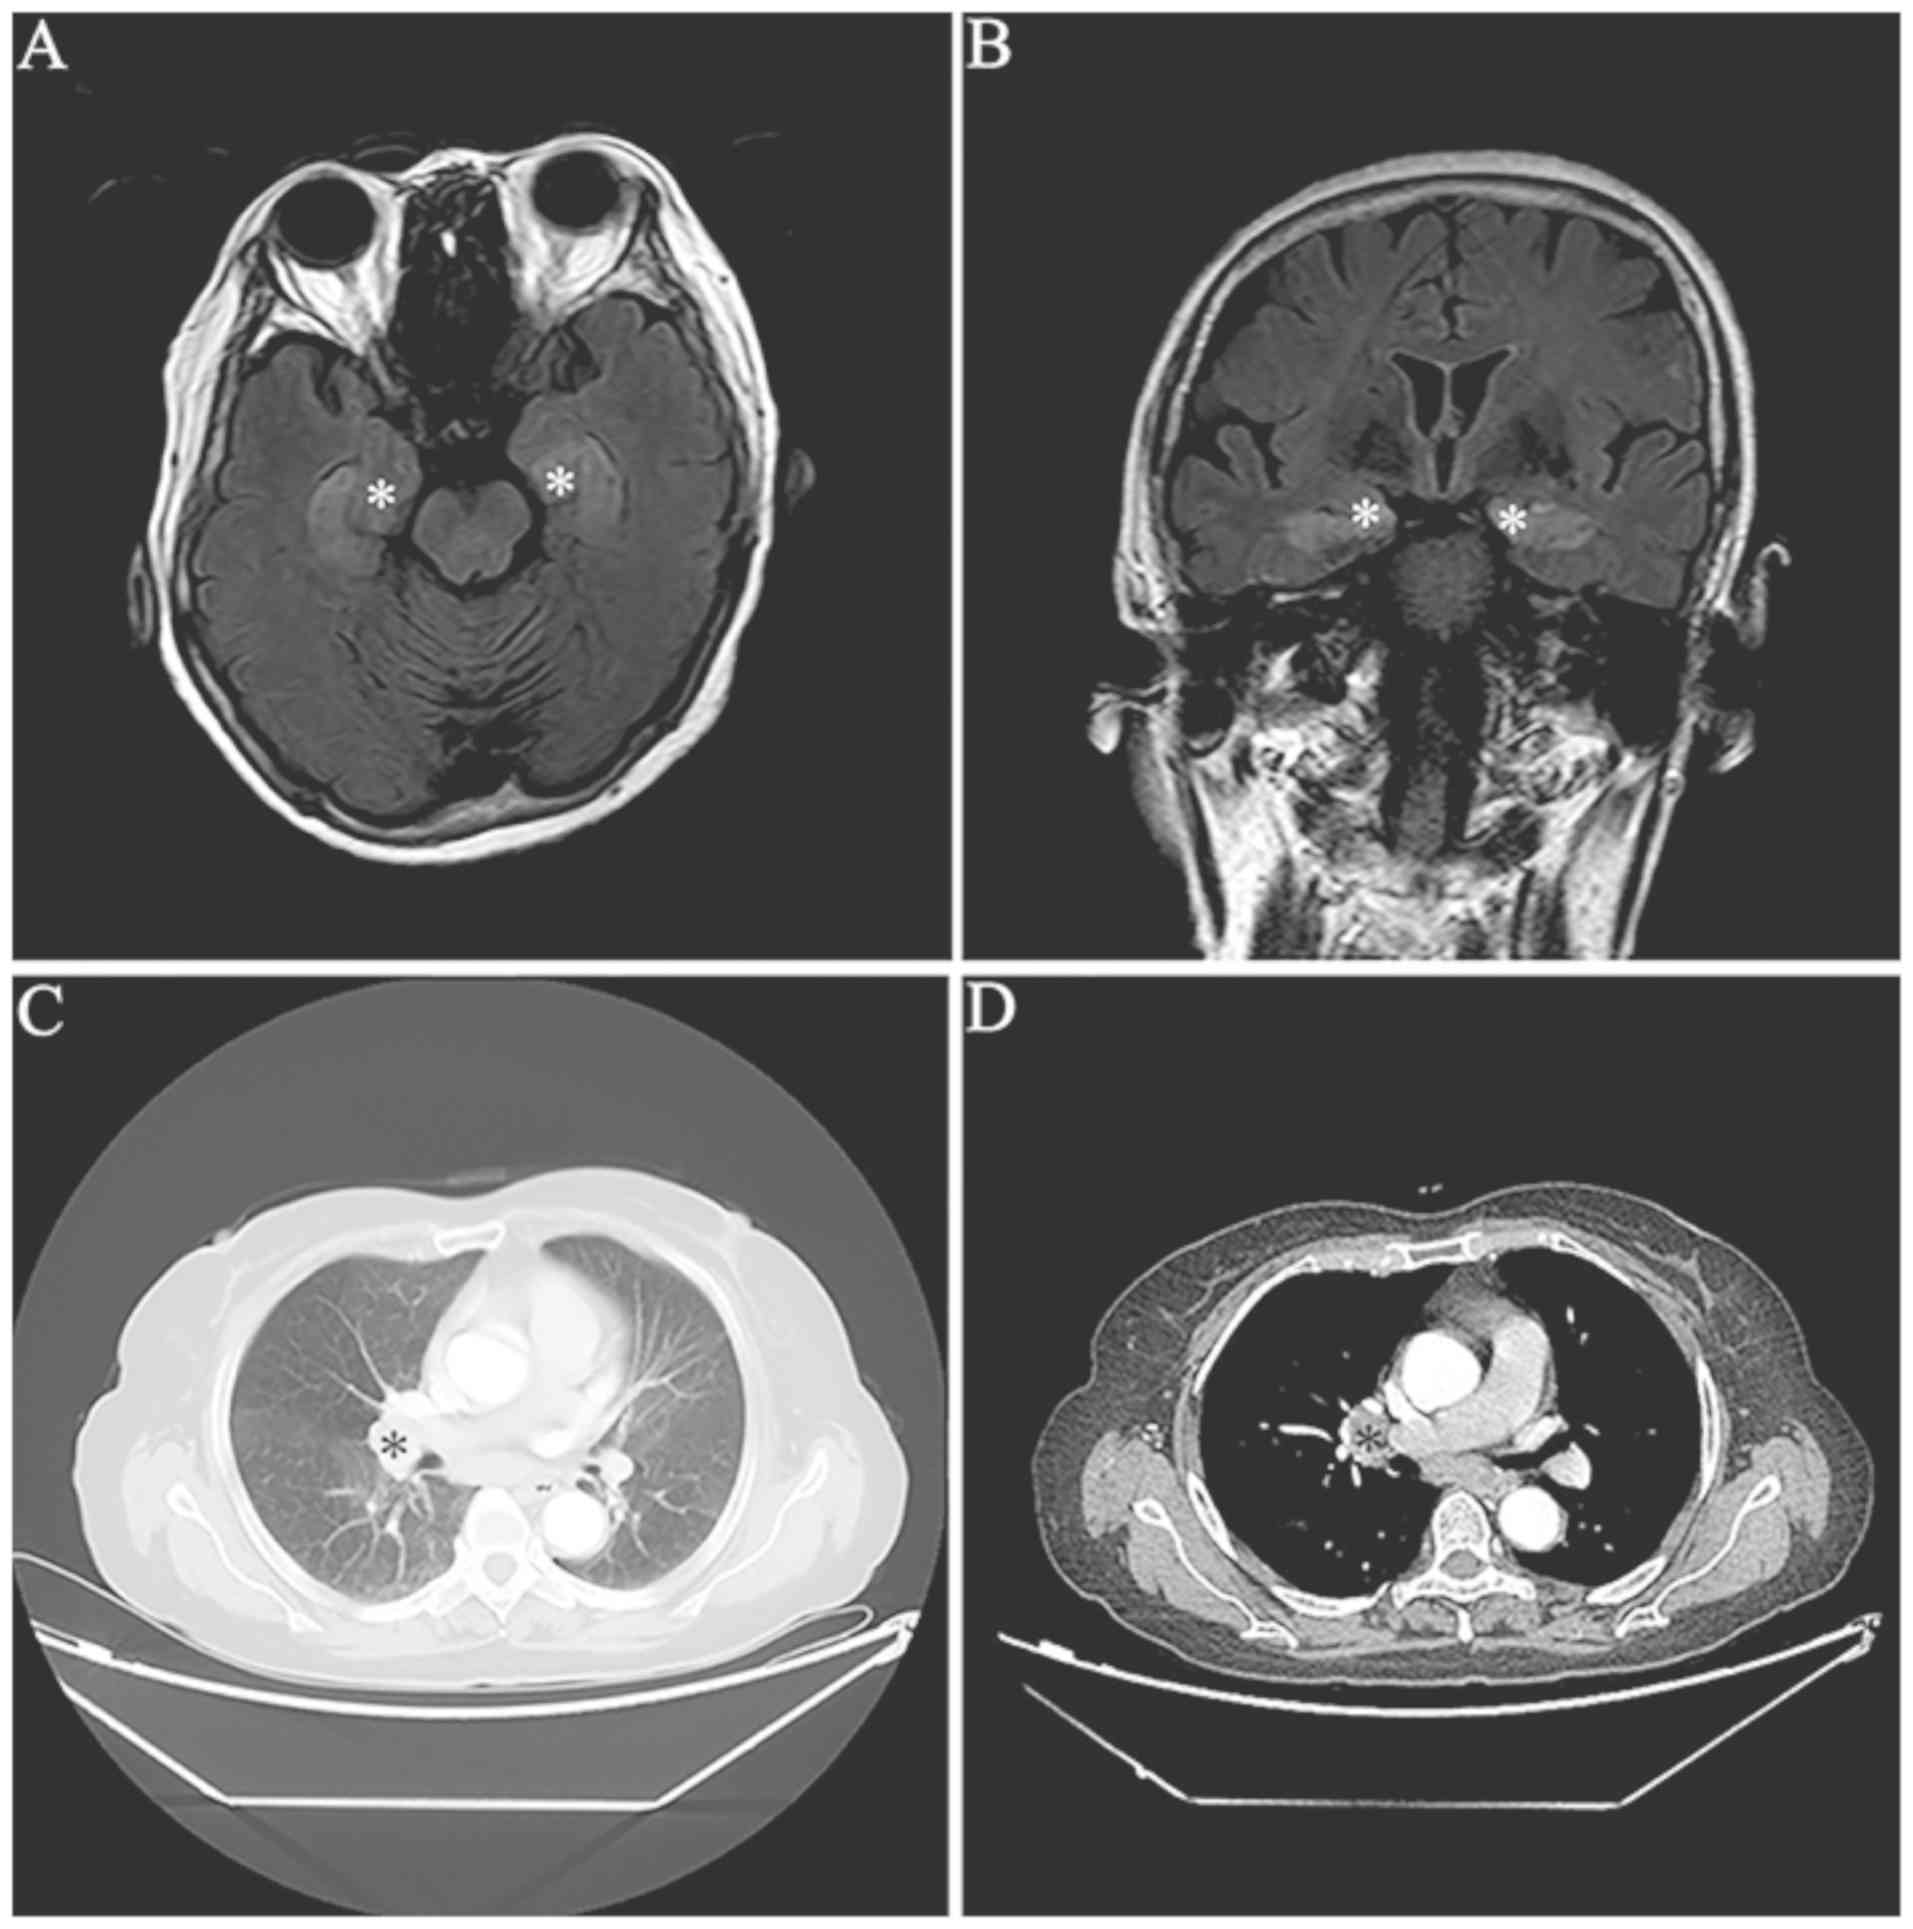

MRI scans demonstrated abnormalities in mesial temporal regions on T2-weighted and fluid-attenuated inversion recovery MRI sequences in four patients (33.3%) (Fig. 1). Furthermore, three patients exhibited bilateral abnormalities and one patient had unilateral abnormalities. It was identified that two patients (16.7%) had diffused cortical atrophy. In addition, EEG examination results were available for 11 patients. It was demonstrated that there were temporal lobe epileptic activities in six patients (6/11; 54.5%) and general slow waves in 10 patients (10/11; 90.9%; Table I).

Figure 1

Images of one limbic encephalitis patient with anti-γ-aminobutyric acid B receptor antibody. (A) Transverse and (B) coronal sections of MRI fluid-attenuated inversion recovery sequence indicate increased signals in the bilateral mesial temporal lobes (white asterisks). (C and D) Thorax CT revealing one mass in the right lung hilus on (C) pulmonary and (D) mediastinal window image (black asterisks).

All patients received tumor screening by CT scans. Lung cancer was detected in seven patients (58.3%) (Fig. 1). Furthermore, tissue pathology exams indicated that two patients had SCLC and one patient had neuroendocrine adenocarcinoma (Table I). It was revealed that the lung cancer tissues of these three patients were positively stained for anti-GABAB receptors by immunohistochemistry (Fig. 2). However, the other four patients with tumors refused further pathological examinations and surgical treatments.